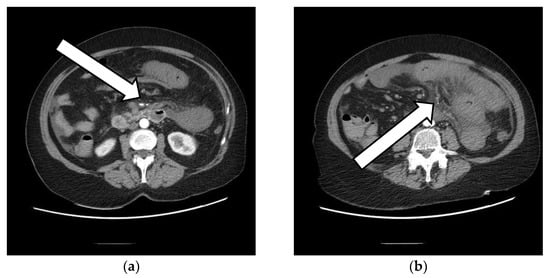

Portal Vein and Mesenteric Artery Thrombosis Following the Administration of an Ad26.COV2-S Vaccine—First Case from Romania: A Case Report

2. The Case Presentation